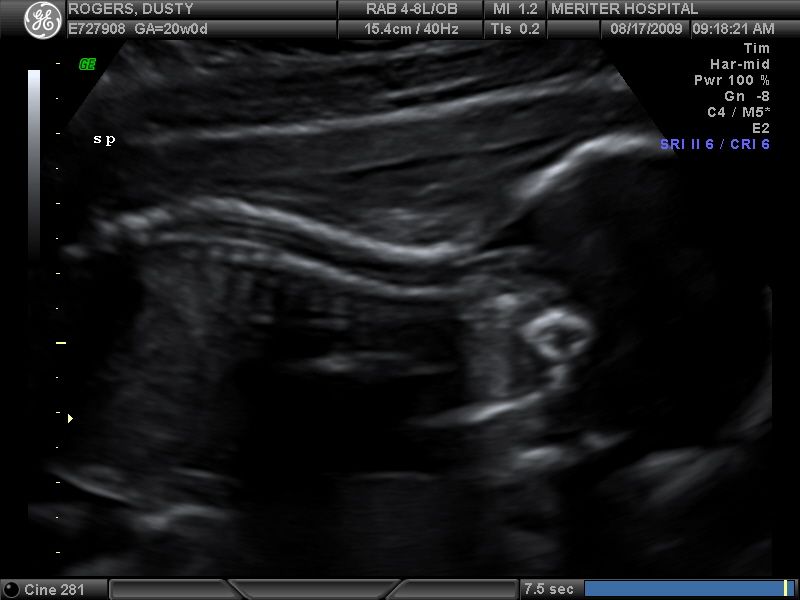

She kept her chin tucked down into her chest during most of the ultrasound, so we couldn’t get a really good look at her face, but here she is–just hanging out in the womb! Here you can see her head (more of a profile view) looking down, her shoulders, chest, and her arms at her sides.